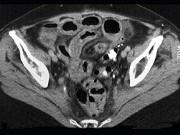

问题 女,54岁,直肠癌放疗后1月,阵发性腹痛腹胀,呕吐应,CT表现如图,应诊断为()

选项 A.小肠淋巴瘤 B.小肠结核 C.小肠Crohn病 D.放射性小肠炎 E.肠易激综合征

答案 D